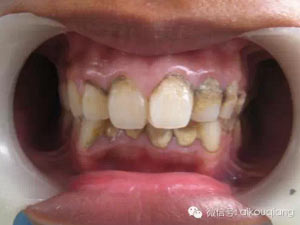

一個高職學(xué)校的學(xué)生,口腔內(nèi)嚴(yán)重的牙結(jié)石,可能小時候沒有刷過牙

7.jpg